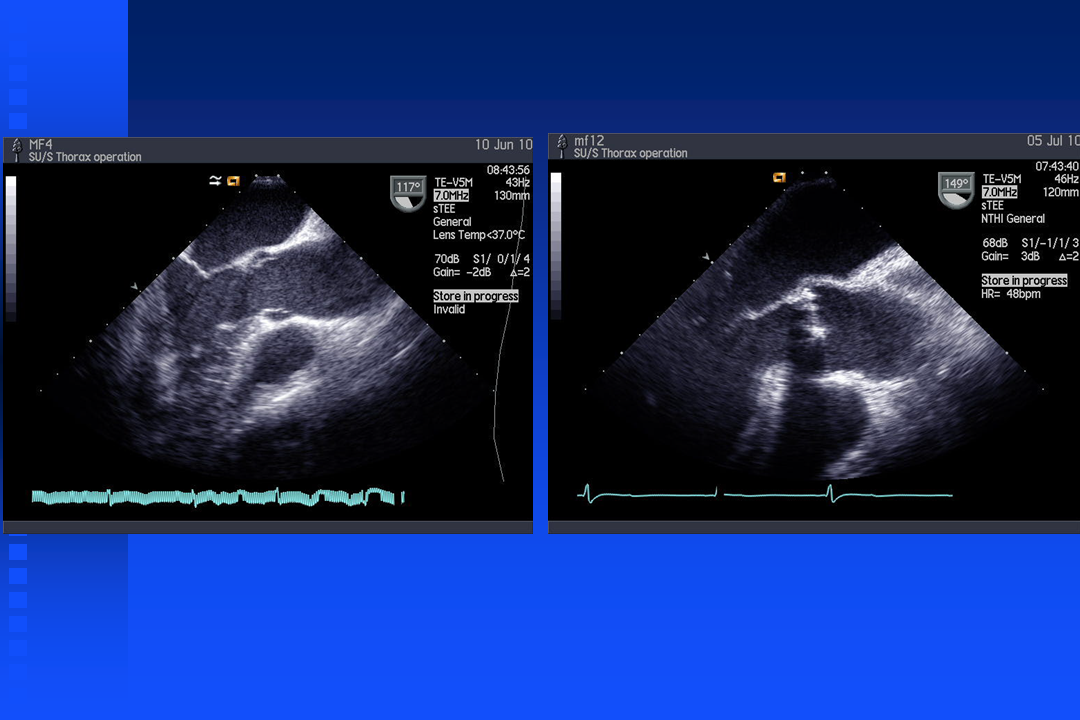

Short film Bicuspid Valve

Short film aortic valve with regurgitation

Short film mitral relaps

Short film mitral relaps with color doppler